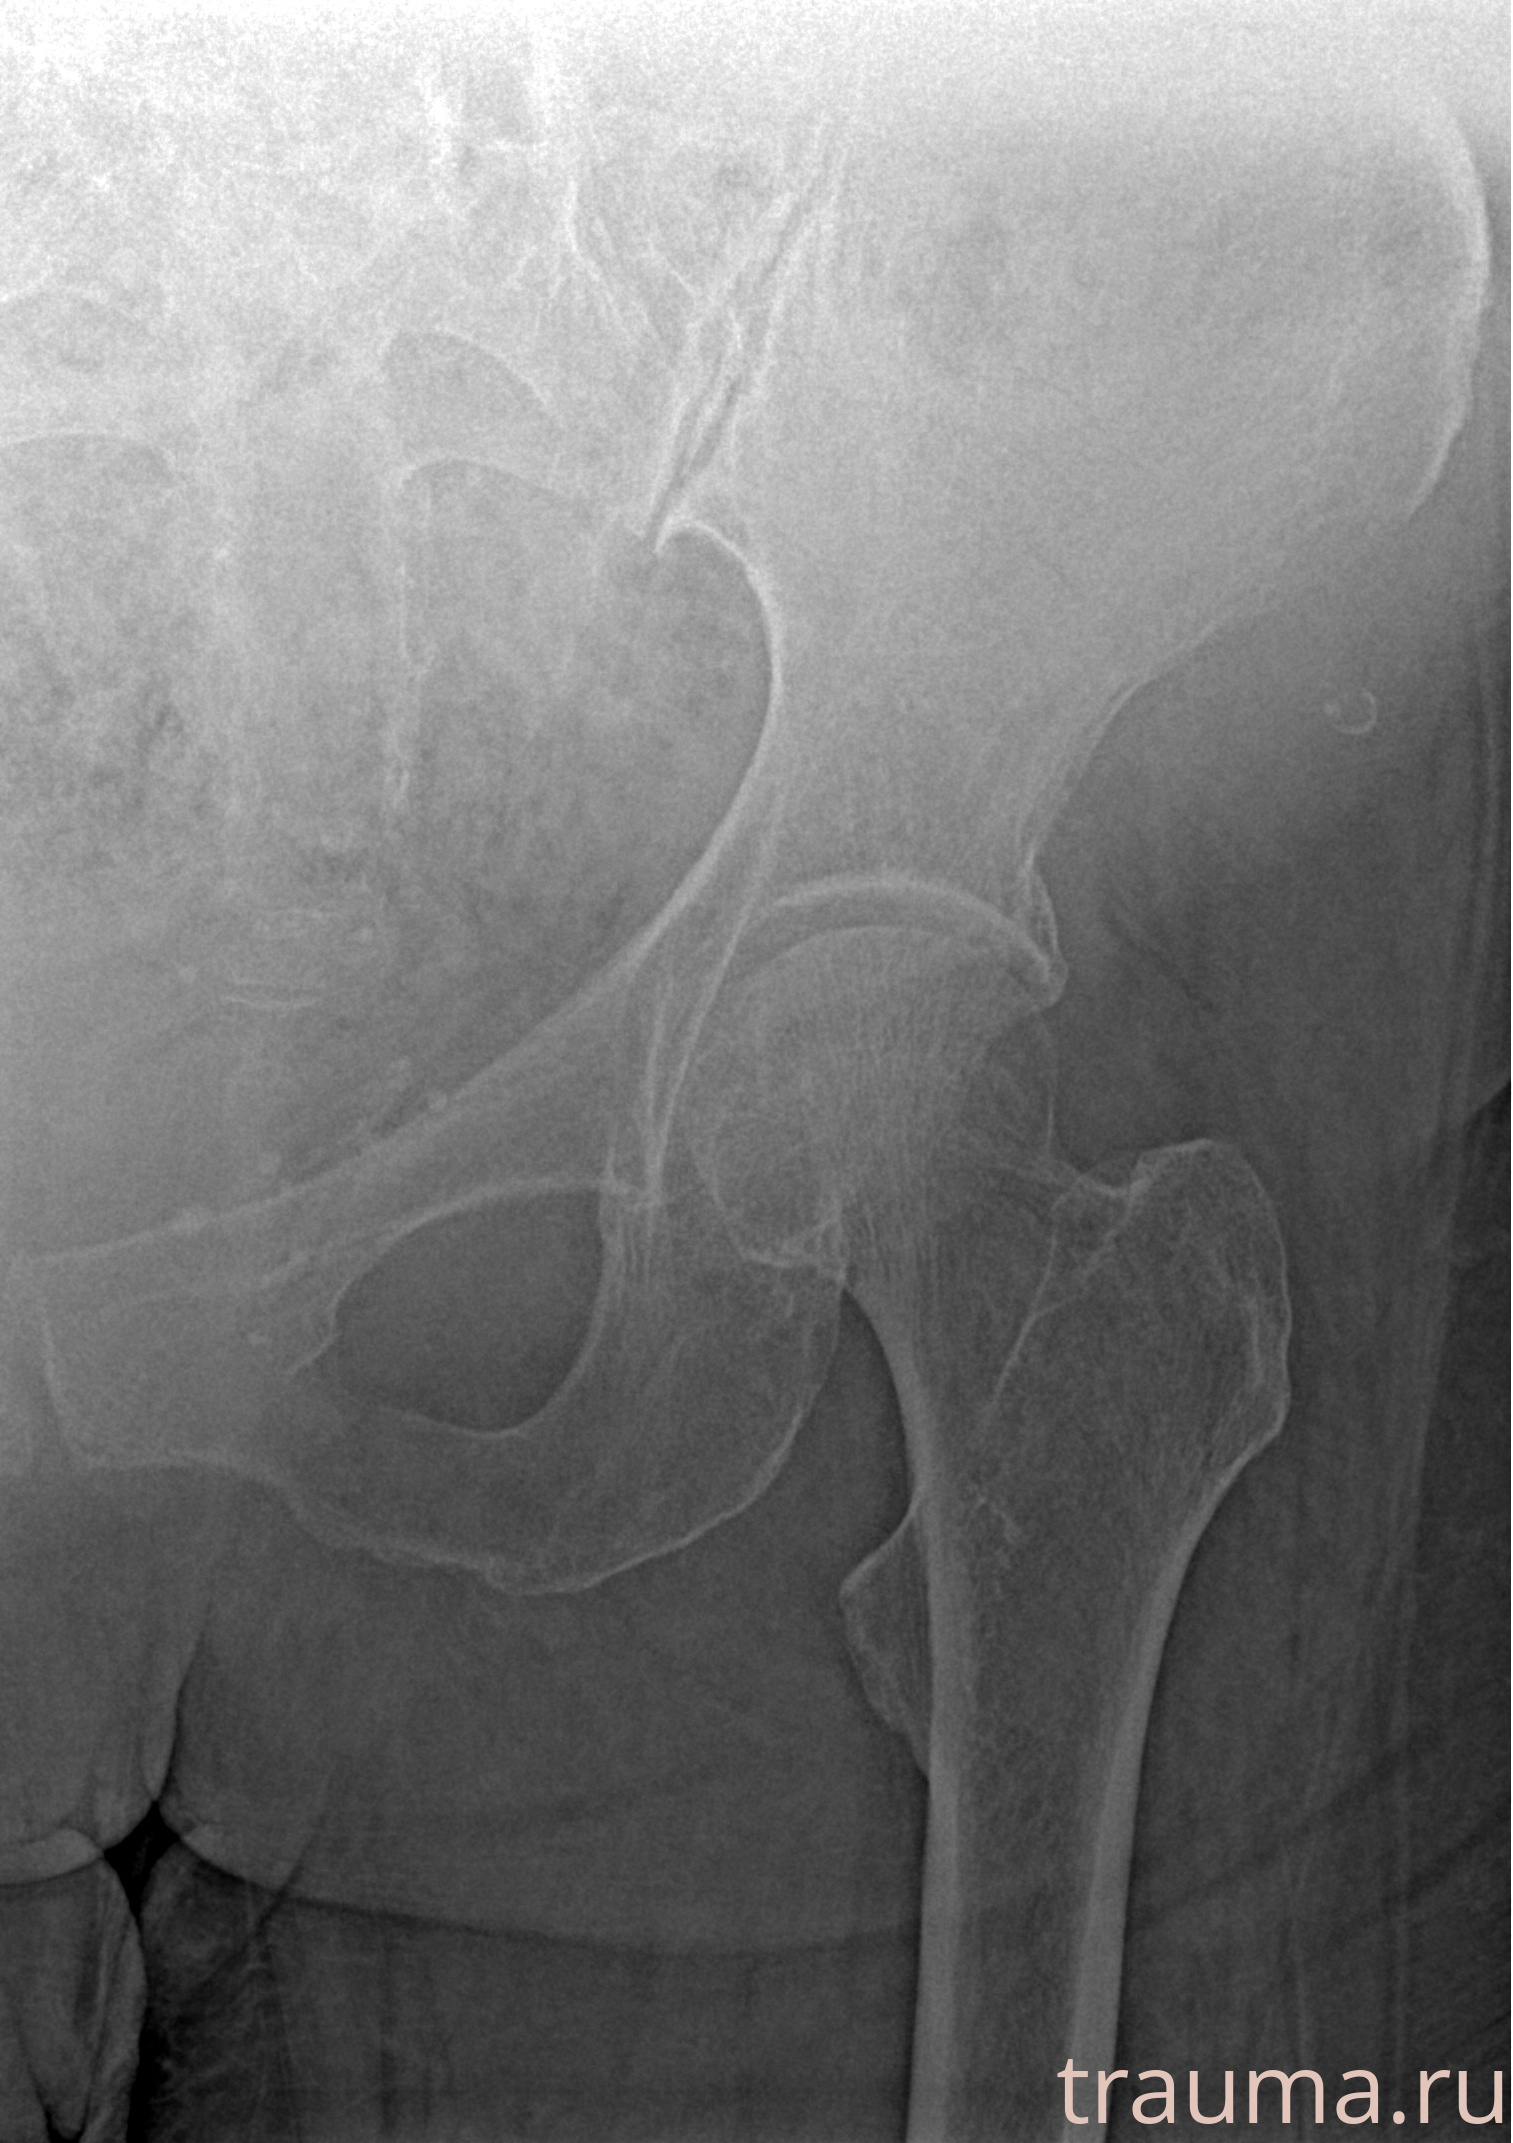

Первая помощь при переломе шейки бедра

Рентгенограммы

Рентген на дому: по вашему адресу приезжает врач-рентгенолог, травматолог-ортопед с мобильным рентгеновским аппаратом, проводит диагностику травмы или заболевания, делает необходимые рентгенограммы, дает рекомендации по дальнейшему лечению. Получить качественные снимки в домашних условиях возможно благодаря уникальной методике, разработанной МосРентген Центром для института  Склифосовского